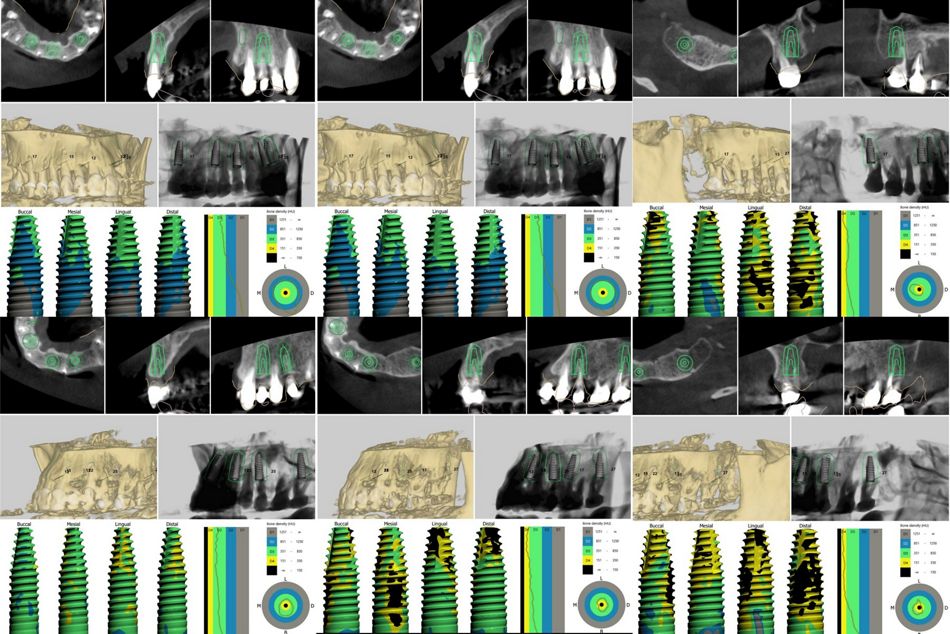

В процессе сбора семейного анамнеза выяснено, что родители пациентки страдали хроническим пародонтитом. Пациентка выросла на крайнем севере России, где был ограниченный пищевой рацион (из-за труднодоступности местности) и очень плохой состав воды, в первую очередь - недостаточное содержание фтора. Еще из факторов риска – курение; нерациональное протезирование и, как следствие, неравномерное распределение жевательной нагрузки; снижение высоты прикуса; наличие большого количества поднутрений, нависающих краёв реставраций, гиперконтуров, недостаточная точность прилегания коронок; неудовлетворительная гигиена полости рта. Десны воспаленные, отечные, имелись пародонтальные карманы разной степени выраженности у всех зубов. КЛКТ выявила тяжелую степень атрофии костной ткани, дефекты костной ткани в области фуркаций, расширение пространства периодонтальной связки у множества зубов. (Илл. 5)

До начала лечебных мероприятий была проведена диагностика, КЛКТ обеих челюстей, интраоральное сканирование. Совместное обсуждение и планирование осуществлялось с главным врачом клиники, хирургом-имплантологом Валинуровым Шамилем Альфатовичем. После изучения всех данных диагностики, обсуждения ситуации с пародонтологом и хирургом, согласования плана лечения с пациенткой, было принято решение об удалении всех зубов и установке 12 имплантатов и интраоперационной установке SRA-абатментов Straumann®️ с последующей ранней нагрузкой этих имплантатов

На основе эстетического и функционального моделирования и планирования были определены позиции имплантатов, в программном обеспечении созданы хирургические шаблоны под полный протокол. (Илл. 6–7)